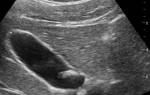

Диагноз желчнокаменной болезни устанавливается на основе различных методов исследования, включая клинические, физикальные, лабораторные и инструментальные данные. Один из основных инструментальных методов — ультразвуковое исследование (УЗИ) органов брюшной полости. УЗИ позволяет обнаружить конкременты в желчных путях в большинстве случаев, но может не выявить обтекаемые камни. Обзорная рентгенография живота может обнаружить камни, содержащие кальций, но не может выявить холестериновые камни. Эндоскопическая ретроградная холангиопанкреатография (ЭРХПГ) используется для визуализации камней, закрывающих общий желчевыносящий и панкреатический протоки. Внутривенная холангиография также может быть проведена, но ее информативность ограничена и она используется только в сомнительных случаях.